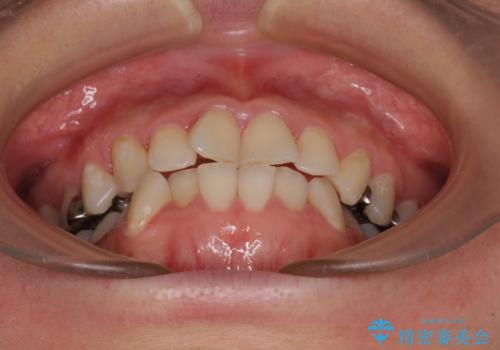

- 治療途中の奥歯の治療継続と、前歯のデコボコを気にして来院された患者様です。

下顎犬歯のクロスバイトが認められ、インビザライン矯正ではクロスバイト改善に伴い奥歯が噛みにくくなることが予想されたため、上下顎間ゴムを積極的に使用して咬み合わせの安定を図ることとしました。